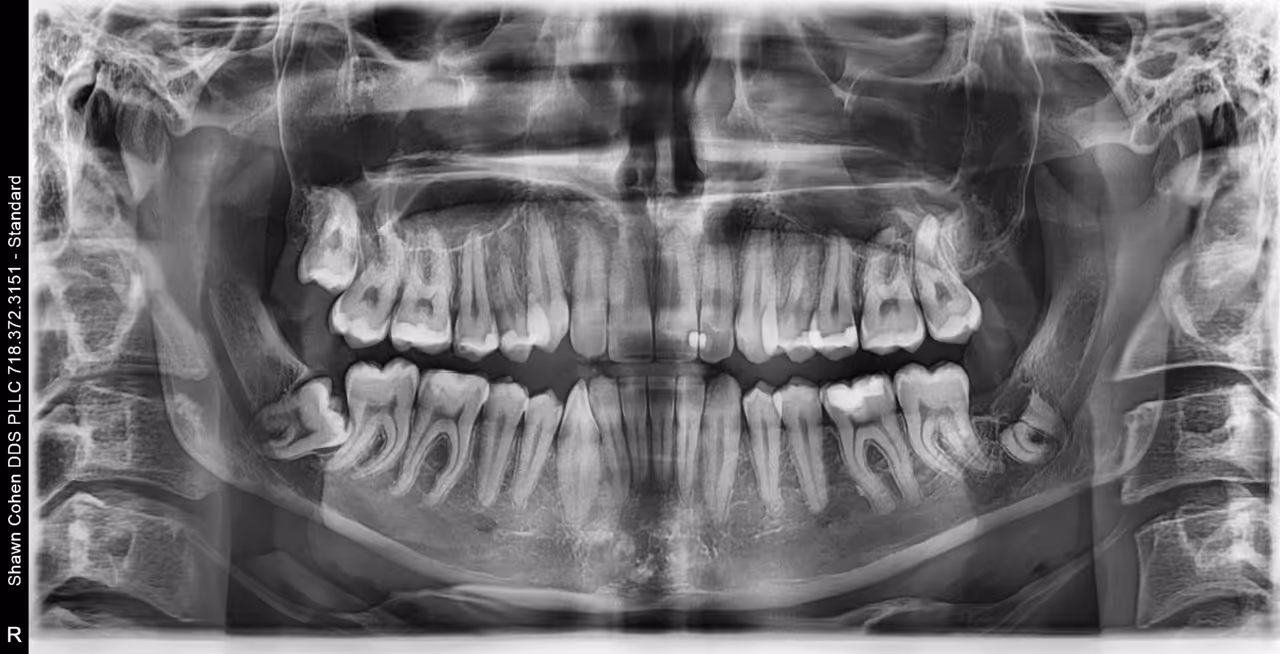

A 3D CT dental scan, also known as Cone Beam Computed Tomography (CBCT), is an advanced, low-radiation imaging technology that creates detailed, 3D digital models of teeth, jawbones, nerve pathways, and soft tissues in seconds. It provides superior accuracy over traditional 2D X-rays for planning implants, oral surgery, and diagnosing complex dental issues.

Although it is not meant solely to detect or diagnose dental caries (cavities), it is used as an adjunct to conventional dental radiographs or 2D X-rays for a more comprehensive evaluation. When necessary, it is an invaluable piece of technology that is safe for patients of all ages based on clinical need.

CBCT is primarily used for complex dental situations where standard X-rays do not provide enough information.

- Surgical Extractions: Specifically for impacted wisdom teeth, it helps locate nearby sensory nerves to minimize the risk of injury. Explore related wisdom teeth extractions.

- Endodontics (Root Canals): Used to identify unusual tooth anatomy, hidden infections, or fractures that are invisible on traditional films. See how this supports root canal therapy.

- Pathology Detection: It can reveal cysts, tumors, or abscesses in the jawbone, sinuses, or nasal cavity, supporting early and accurate diagnosis as part of our comprehensive oral surgery services.